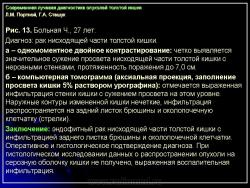

Отображение опухоли толстой кишки на компьютерных томограммах зависит от локализации процесса и характера роста. При преимущественно диффузном внутристеночно растущем раке кишки, что выявлялось гораздо чаще, при КТ отмечалось утолщение стенки кишки с неравномерным, достаточно часто циркулярным сужением просвета соответствующего участка ее, ригидностью стенки (отсутствием изменения диаметра просвета и толщины стенки при дозированном введении воздуха) и неровными внутренними контурами (рис. 11). При экзофитном характере роста опухоли при КТ внутри просвета кишки определялось дополнительное мягкотканное образование с неровными бугристыми контурами, широко прилежащее к стенке кишки. Опухоли были различной структуры: однородной, неоднородной за счет включений кальция или участков распада с наличием в опухолевой ткани жидкости и газа. При появлении газа в околокишечной клетчатке чаще всего предполагалась перфорация ее стенки. Кроме оценки состояния стенок кишки, пораженной опухолью, оцениваются и изменения в окружающих тканях и органах при распространении ее за серозную оболочку. Степень местного распространения опухоли является одним из определяющих факторов прогноза и выбора дальнейшей тактики лечения. Оценку степени распространения опухоли проводили в соответствии с Международной классификацией по системе ТNM.

Распространение на смежные органы и висцеральную брюшину (Т4) диагностировалось на основании симптомов “дополнительного узлового объемного образования” по наружному контуру кишки в зоне опухолевого поражения, выраженной инфильтрации клетчатки, брыжейки, отсутствия границ между измененной стенкой кишки и прилежащими органами. На выявление инвазии опухоли в окружающие органы влияет количество жира: чем его меньше, тем труднее диагностика. Очень помогает выявлению распространенности опухолевого процесса на смежные органы и структуры проведение полипозиционного исследования, заполнение прилежащих полых органов (петель тонкой кишки, полости мочевого пузыря) контрастными смесями или газом. Признаками метастазирования опухоли кишки в лимфатические узлы брюшной полости и забрюшинного пространства считались увеличение их диаметра более 15 мм и склонность к слиянию в конгломераты. Однако при высокой чувствительности выявления увеличенных лимфатических узлов по данным КТ (до 95%), специфичность этого метода, как и других – УЗИ, МРТ, остается достаточно низкой (до 33%). В то же время выявление метастазов в печень характеризуется достаточно высокой специфичностью метода (до 99,6%) и чувствительностью (до 73%). Это относится к метастазам, диаметр которых в основном более 10–12 мм. Метастатические очаги в печени меньших размеров (до 5–7 мм) диагностировать значительно сложнее. Как и другие авторы, мы считаем, что КТ не должна применяться в качестве метода первичной диагностики опухоли, но она дает значительный объем дополнительной информации о распространенности опухоли и особенностях ее роста. Особую ценность КТ имеет при выраженных опухолевых стенозах, когда невозможно использовать другие методы диагностики, в том числе и эндоскопию, а иногда и традиционные рентгенологические методики. Поэтому КТ – это один из основных методов повышения точности и полноты диагностической информации, позволяющих диагностировать стадию опухолевого процесса до проведения операции, что определяет выбор схемы лечения и, следовательно, прогноз его результатов.